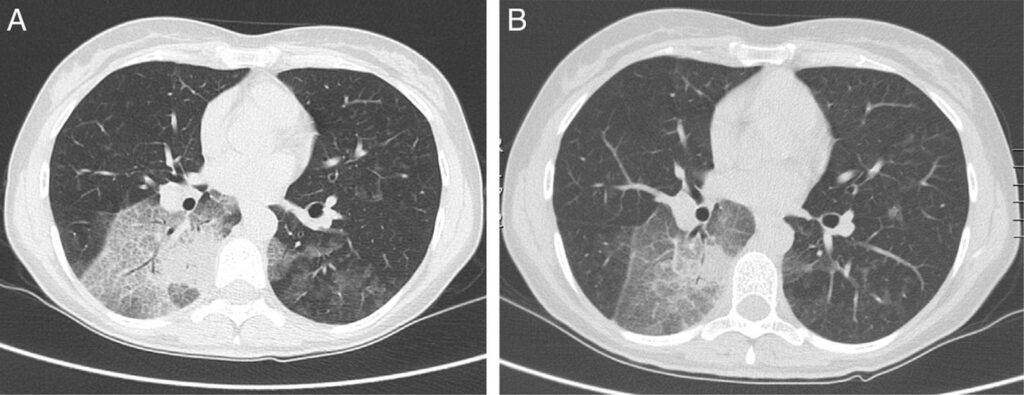

Den primære billeddiagnostiske metode er en højopløselig computertomografi (HRCT-scanning) af brystkassen. På en HRCT-scanning kan lægen se karakteristiske forandringer, såsom områder med lav tæthed (der indikerer fedt) i lungevævet. Selvom disse fund er stærkt suggestive, er de ikke altid definitive.